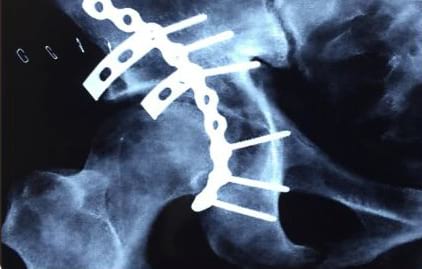

The Trauma Center at Anup Institute of Orthopaedics and Rehabilitation has gained significant expertise in managing complex cases, including pelvi acetabular fractures, calcaneal fractures, spine and hand trauma, among others. The department is well-prepared to handle severely injured patients and regularly trains its staff to provide optimal care.